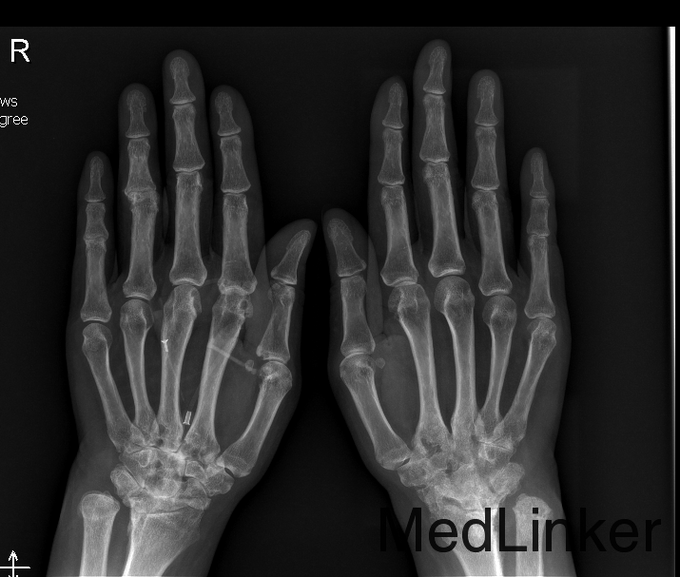

心肺腹查体未见明显异常。双肩关节无压痛,双肘关节压痛+,肿胀+,双腕关节压痛++,肿胀++;关节活动受限,双腕关节及双侧第4、5掌指关节、指间关节畸形,双侧掌指关无压痛,无肿胀;关节活动尚可,双膝关节无肿胀、压痛,皮温无升高,浮膑征-,双踝关节肿胀++,压痛++。 查全血常规正常; 电解质、肾功能正常。 乙肝两对半提示为小三阳,HBV-DNA阴性, 肝功能ALT 67 U/L; 炎症指标:C反应蛋白测定 12.6mg/L ↑; 类风湿因子测定 64.4IU/mL ↑; 红细胞沉降率 20mm/h ; 抗核抗体定性阴性-;抗ds-DNA定量 15.4IU/ml ;ENA抗体阴性-; 补体C3含量测定 695mg/L ↓;补体C4含量测定 178mg/L; 直接抗人球蛋白试验阳性+;间接抗人球蛋白试验阴性; 免疫球蛋白IgA、IgM、IgG均正常; 双足部、双膝关节、手正位放射常规照片:双手、双腕及双足跖趾关节改变,符合类风湿关节炎。